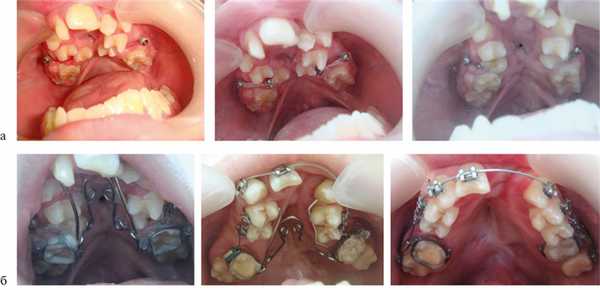

В зависимости от возраста использовали разные методы ортодонтического лечения. В 1-й группе (n=47) на I этапе применяли съемные механически-действующие аппараты, ортодонтические аппараты с винтом Бертони. Нормализация положения верхней челюсти (ВЧ) относительно костей лицевого черепа и стимуляция ее роста в сагиттальном направлении достигались с помощью маски Деляра.

В позднем сменном прикусе использовали частичную брекет-систему «2×4» (20 аппаратов), несъемный капповый аппарат с винтом для расширения ВЧ (3 аппарата). 15 аппаратов Бидермана (RME) для быстрого расширения ВЧ фиксировали на ортодонтических кольцах. Применялся также аппарат Квад-Хеликс (115 единиц). В 4 случаях при выраженной вторичной деформации использовали ортодонтические микровинты и эластичную тягу (2 аппарата).

В период постоянного прикуса у пациентов 2-й и 3-й групп использовали несъемные аппараты для интенсивного расширения верхнечелюстной зубной дуги, брекет-систему.

Деформации зубоальвеолярных дуг устраняли до проведения костной пластики. Для этого использовали аппараты, которые позволяли нормализовать положение резцов, фрагментов АО, положение резцовой кости и в результате создать зубоальвеолярную дугу правильной формы и определить истинный размер расщелины (рис. 2).

Рис. 2. Несъемный дуговой аппарат (система «2×4»). а — динамика перемещения зубов у пациента с ОРГН; б — динамика перемещения зубов у пациента с ДРГН.